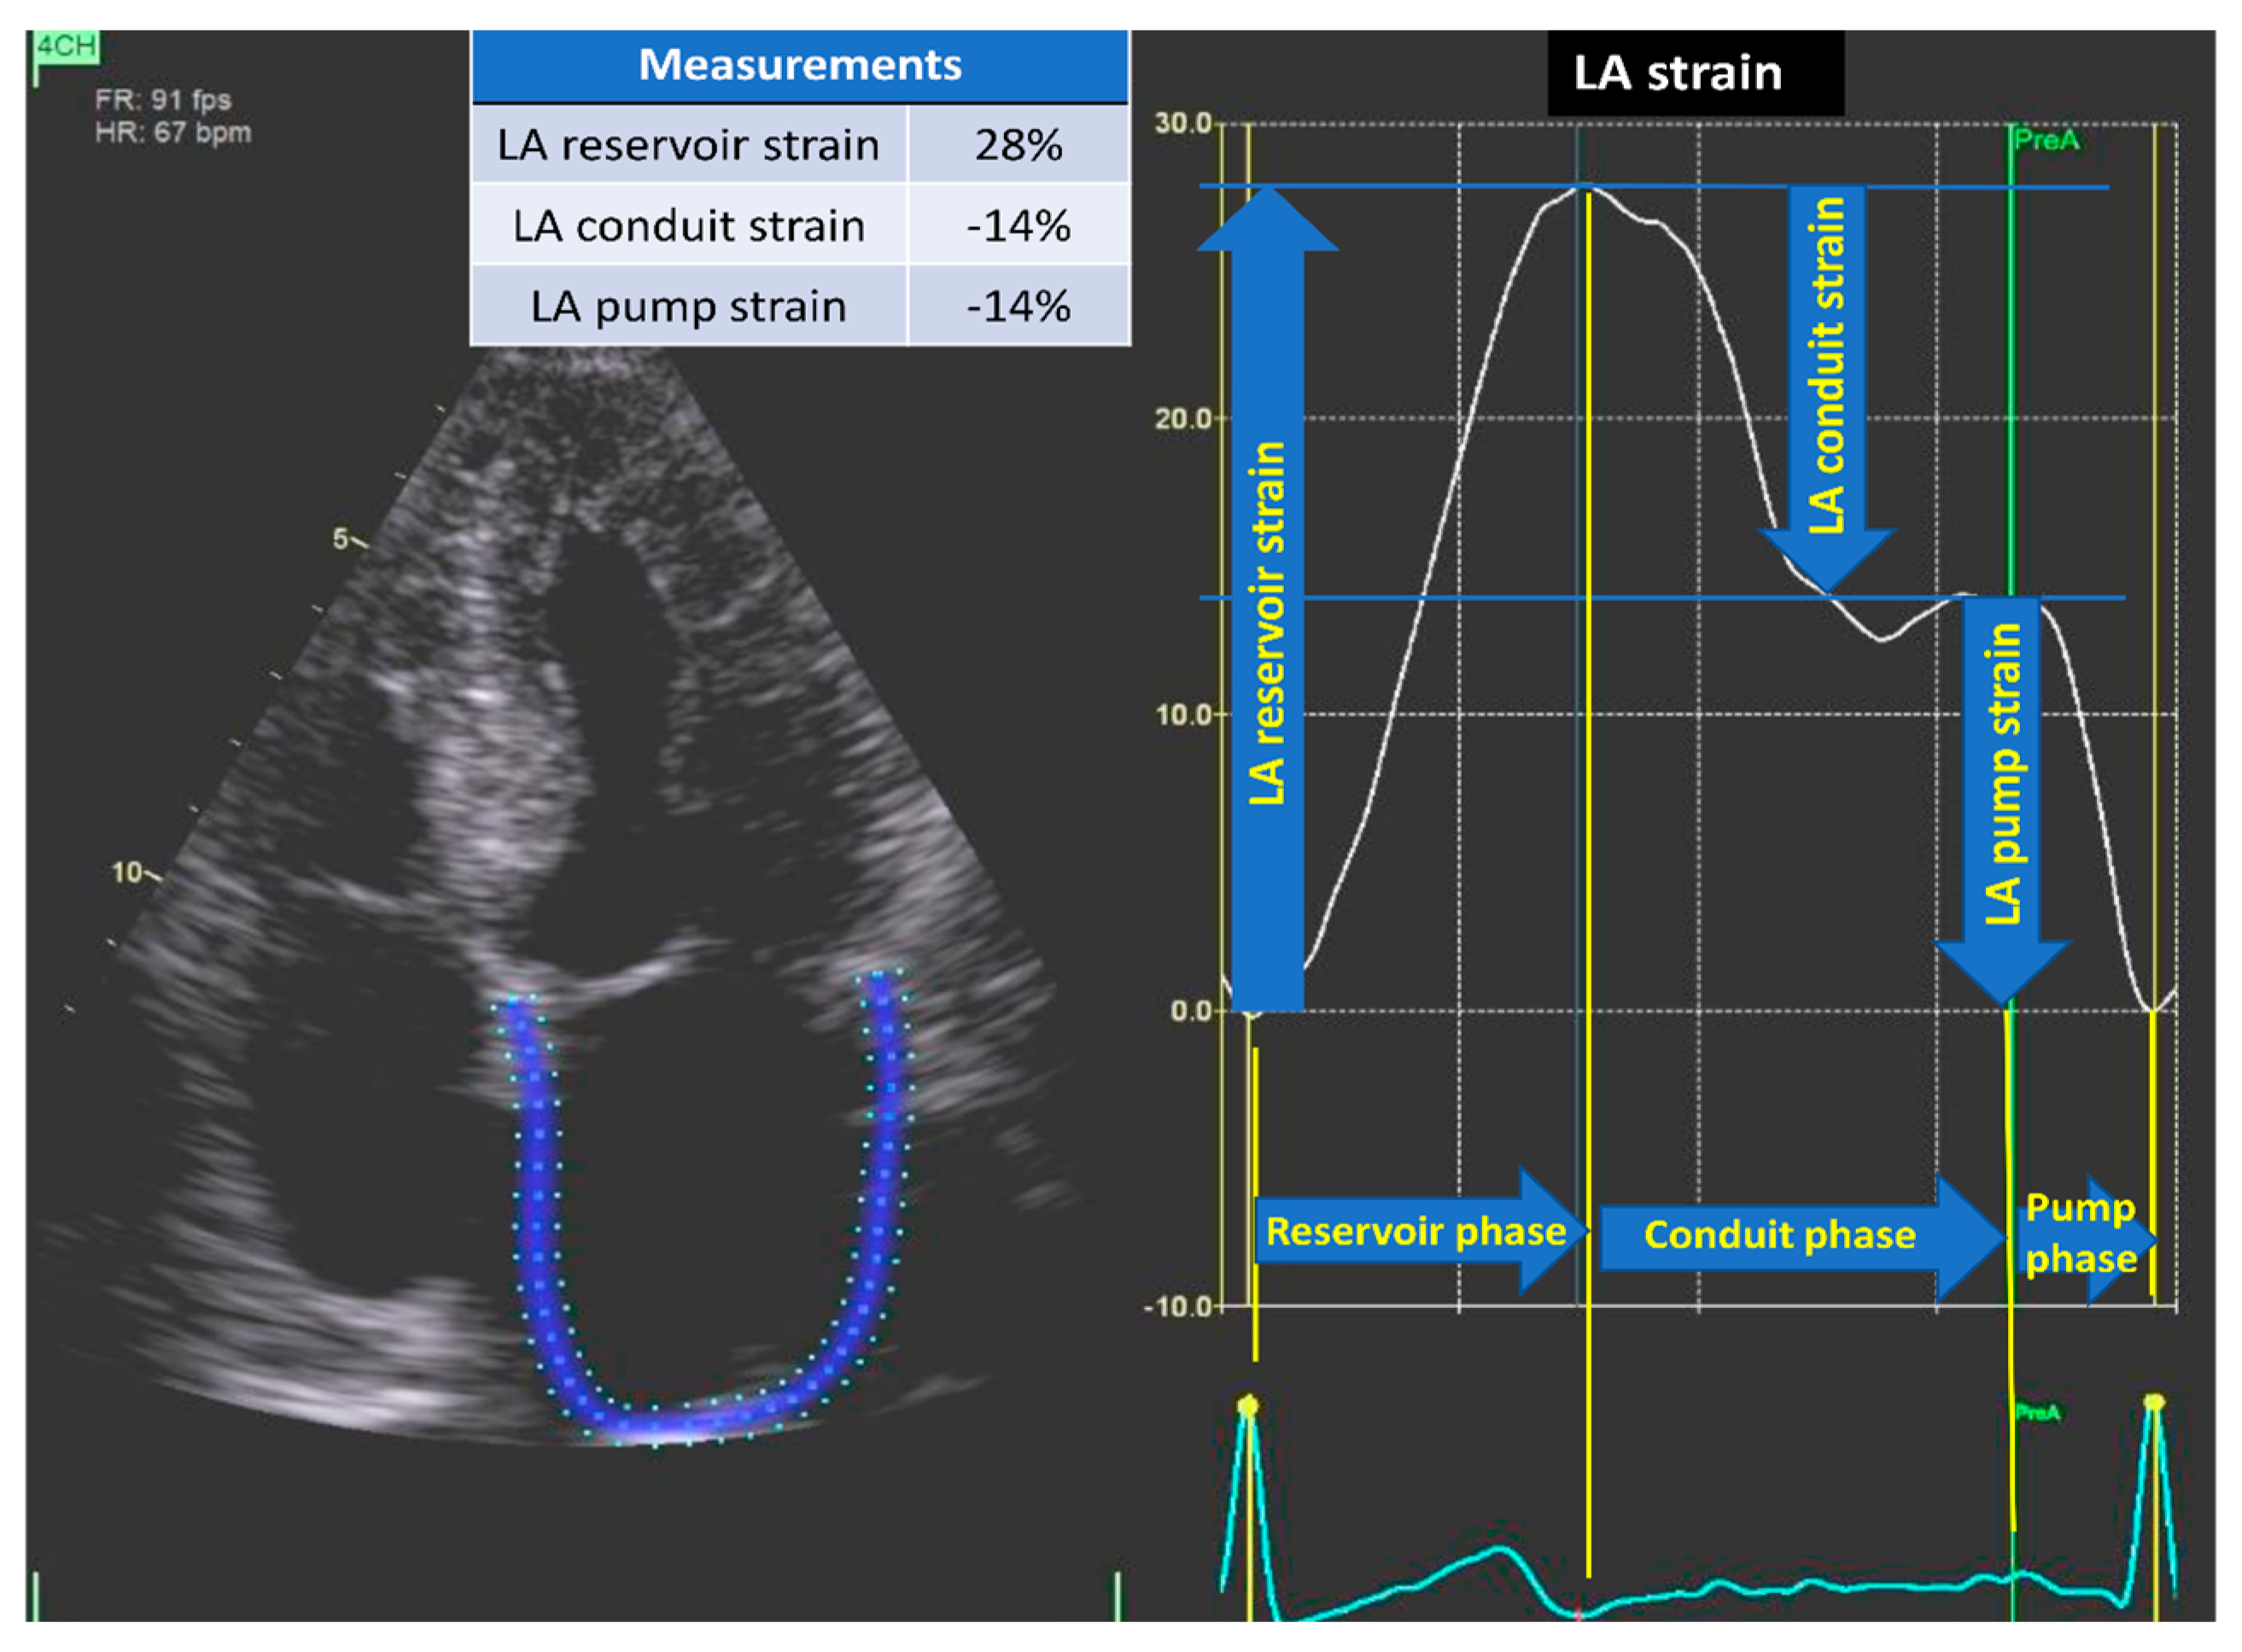

2.4. Left Atrial Function